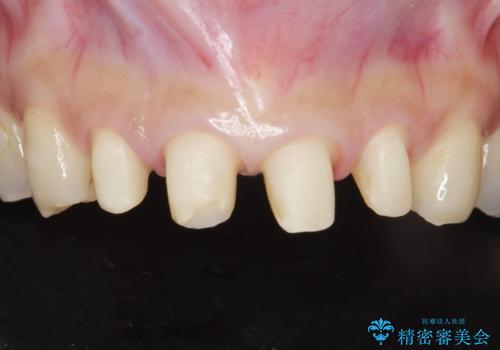

前歯をきれいな被せ物にしたい。

- 前歯の形が気に入らなく、粗造な感じがして色も気に入らないとの事で来院。

ホワイトニングは以前行っていてもうやりたくないとの事でした。

虫歯になっている歯はないので、患者様としっかり相談をして被せ物治療をする事に致しました。

適合の良い被せ物が入りました。

樹脂の素材とは違い、セラミックやジルコニアの素材の被せ物は劣化をしません。また、虫歯の再発リスクも低くなります。

形、色、共に満足して頂けました。